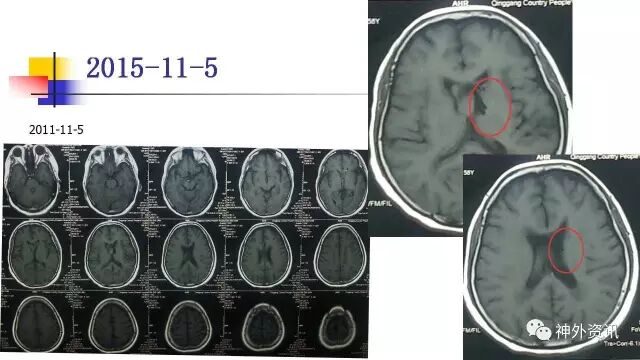

手术过程